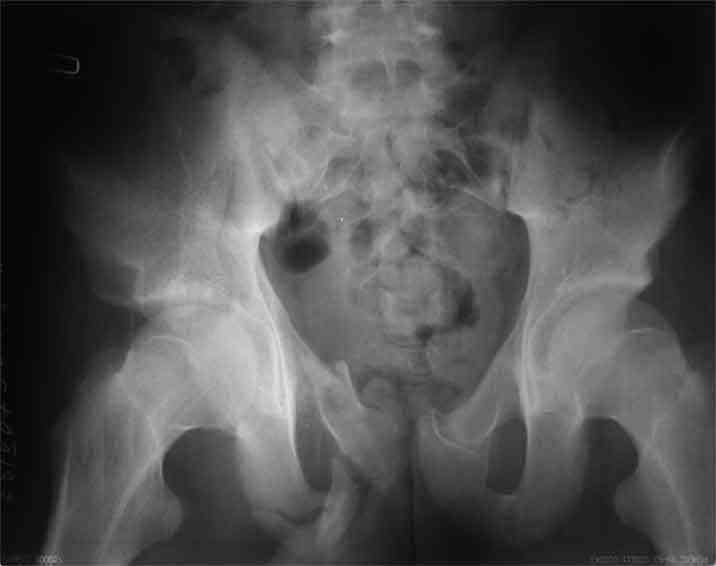

А чего там собственно таинственного? Билатеральное ротационно-нестабильное повреждение таза, перелом крестца в I зоне (по Denis)справа,частичное повреждение левого КПС, оскольчатые переломы лонной, седалищной костей справа (В3.2). Повреждение достаточно стабильное + молодой возраст+ сроки - оперативного лечения не требует.

Не смог разглядеть на представленных картинках частичное повреждение левого КП, повреждение Денис1-2 справа? 3Д реконструкции в инлет и боковой проекциях убедительно не демонстрируют типа повреждения задних отделов тазового кольца(справа боковая масса скомпремирована), Наверное, у тебя есть возможность оценить тип перелома крестца по прямой проекции 3Д.

по Pennal et al.- латеральное компрессионное повреждение тип В(ротационно-нестабильное (внутренняя ротация), вертикально стабильное)

по Tile classif. тип В2-1 - частично стабильное повреждение с неполным разрывом задней дуги.

по-поводу таза особых диагностических сложностей и не было, на некоторых других срезах есть "раскрытие" левого КПС

В данном случае 3D и корональные срезы КТ менее информативны, чем поперечные. Согласен с левосторенним минимальным повреждением КПС, но не смог уловить перелом крестца.

По представленным материалам, мне кажется, перелом был передней колонны ацетабулум с минимальным вовлечением нагрузочной поверхности сустава, левосторенний повреждение КПС и лонных костей.